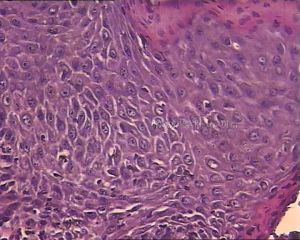

3.組織病理檢查

如在棘層上方及顆粒層出現空泡化細胞,是診斷HPV感染的重要證據。